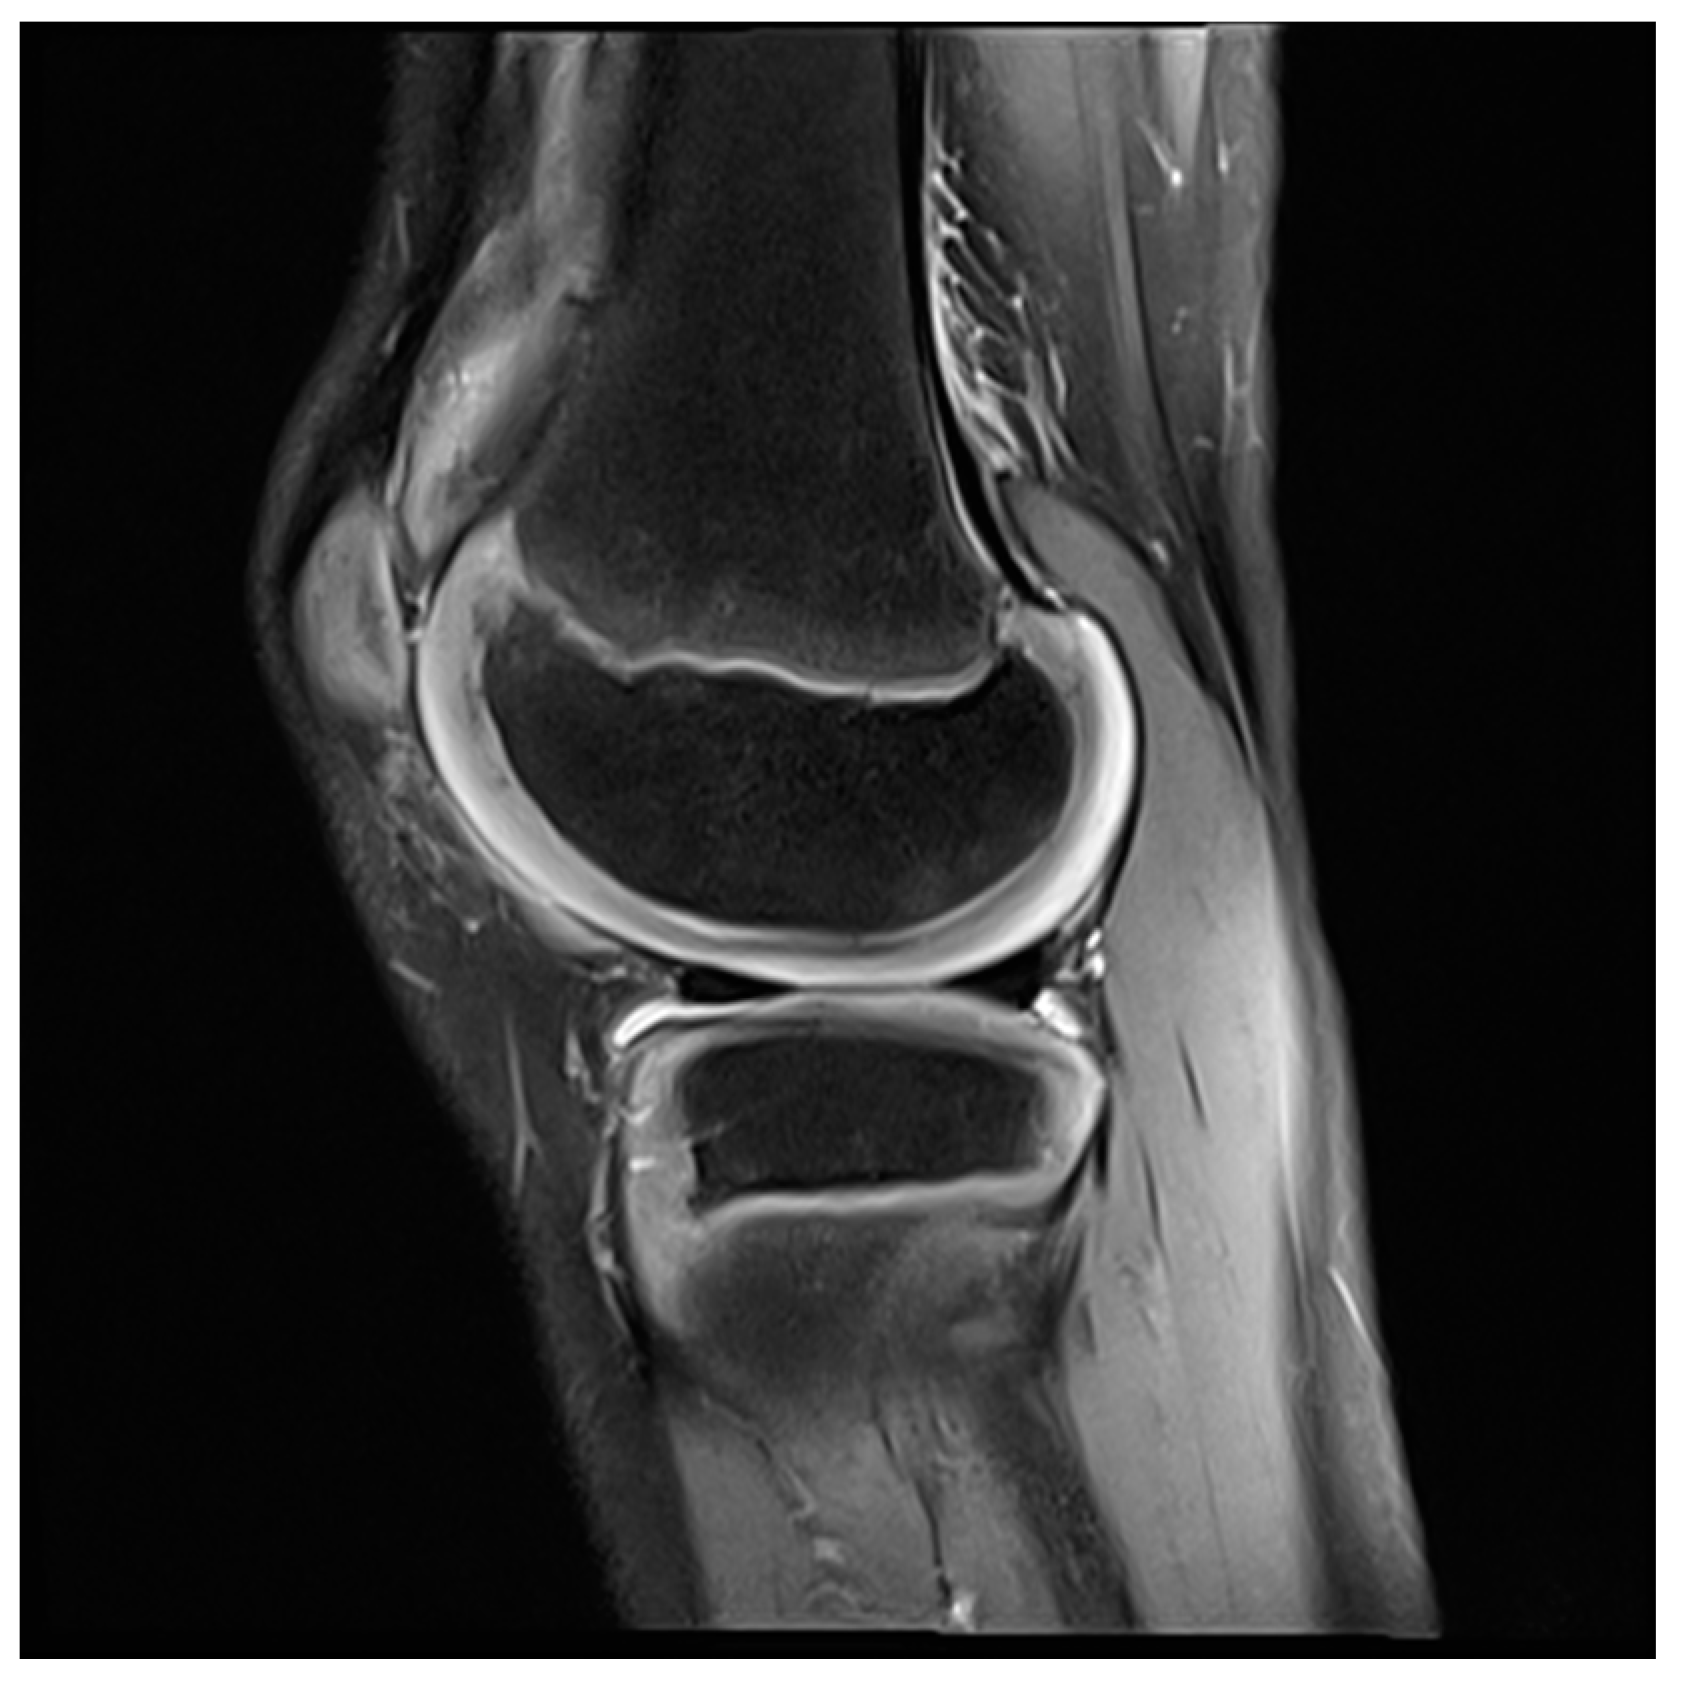

- Hirose, J.; Nishioka, H.; Tsukano, M.; Matsubara, S.; Usuku, K.; Mizuta, H. Matrix changes in articular cartilage in the knee of patients with rheumatoid arthritis after biological therapy: 1-year follow-up evaluation by T2 and T1ρ MRI quantification. Clin. Radiol. 2018, 73, 984.e911–984.e918. [Google Scholar] [CrossRef]